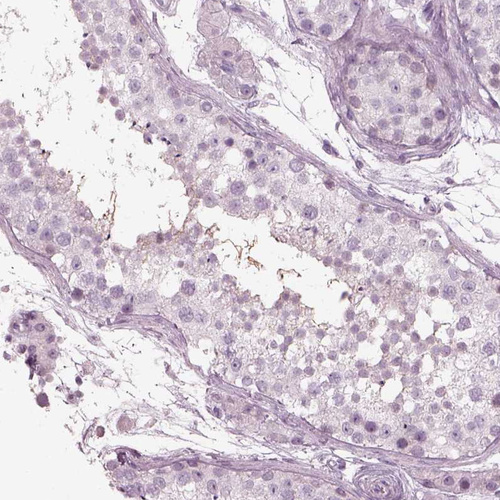

Immunohistochemistry analysis in human fallopian tube and prostate tissues using HPA067155 antibody. Corresponding HYDIN RNA-seq data are presented for the same tissues.